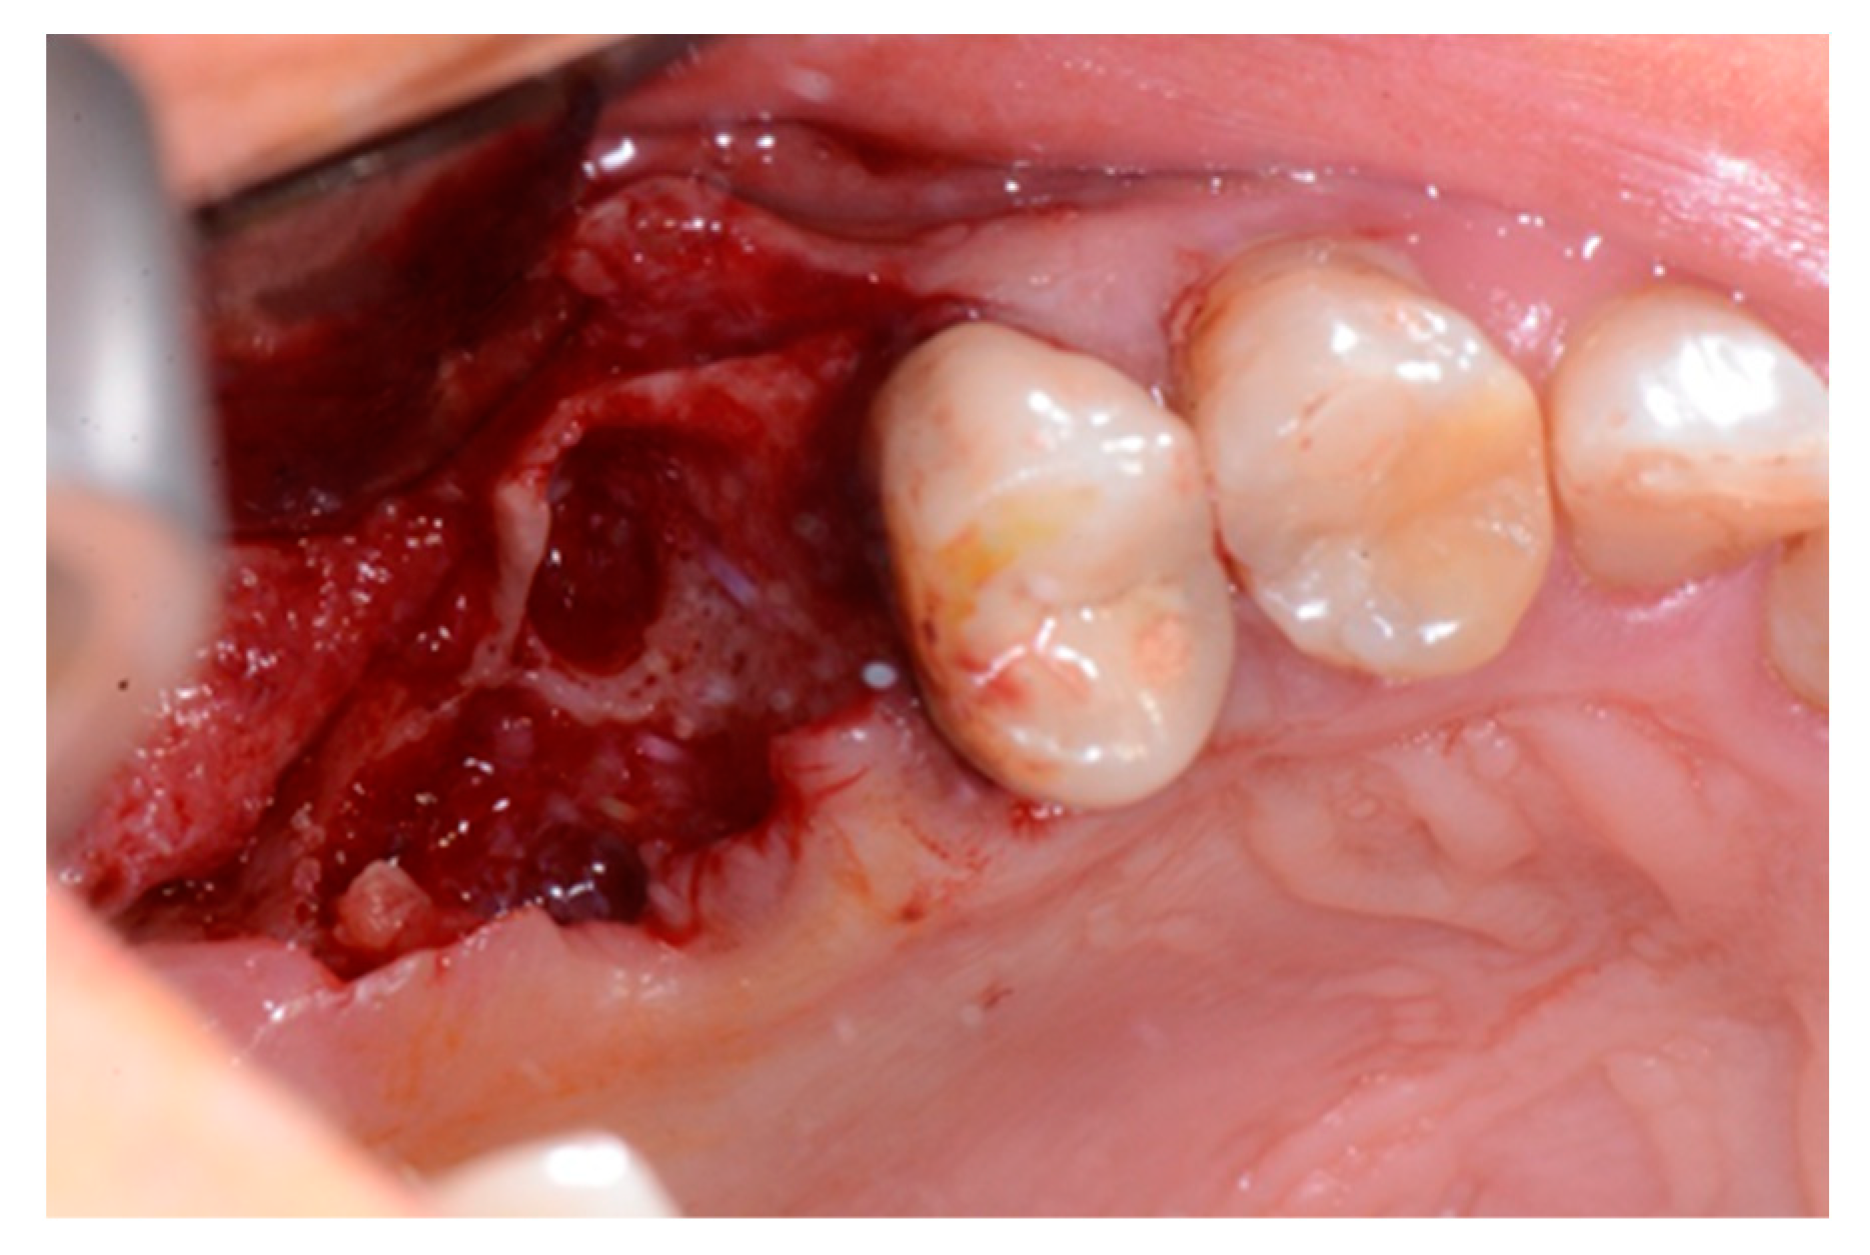

2. Case Report